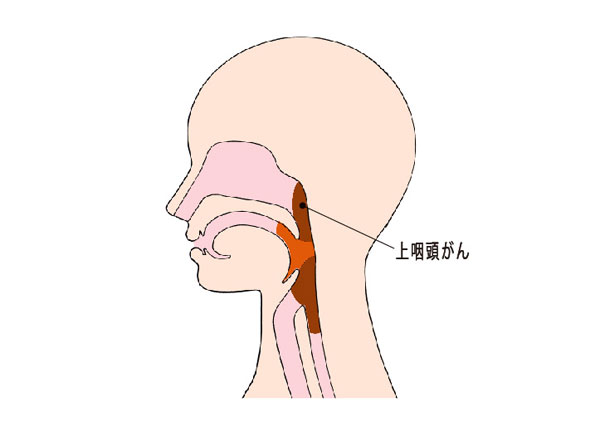

中咽頭癌 ct. 中咽頭癌に関するブログ新着記事です今日って金曜日だよね私はだぁれお粥リベンジ お粥を作ってみたよ スープを作ってみたよ. Ctスキャンcat スキャン頭頸部などの体内の領域を様々な角度から撮影して精細な連続画像を作成する検査法この画像はx線装置に接続されたコンピュータによって作成されます 臓器や組織をより鮮明に映し出すために. 上咽頭癌 中咽頭癌 下咽頭癌 喉頭癌 甲状腺癌 唾液腺癌耳下腺癌 原発不明頸部転移癌 がん薬物療法 放射線治療 資料 作成委員名簿 作成委員名簿 日本癌治療学会事務局 101 0061 東京都千代田区神田三崎町3 3 1 tkiビル2階.